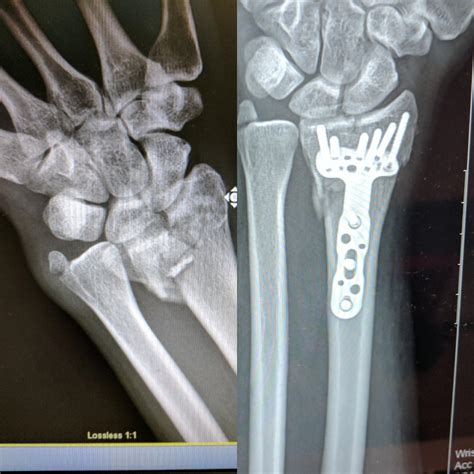

Broken Wrist Distal Radius Fracture: Diagnosis, Treatment, Recovery

Broken Wrist Distal Radius Fracture: Diagnosis, Treatment, Recovery